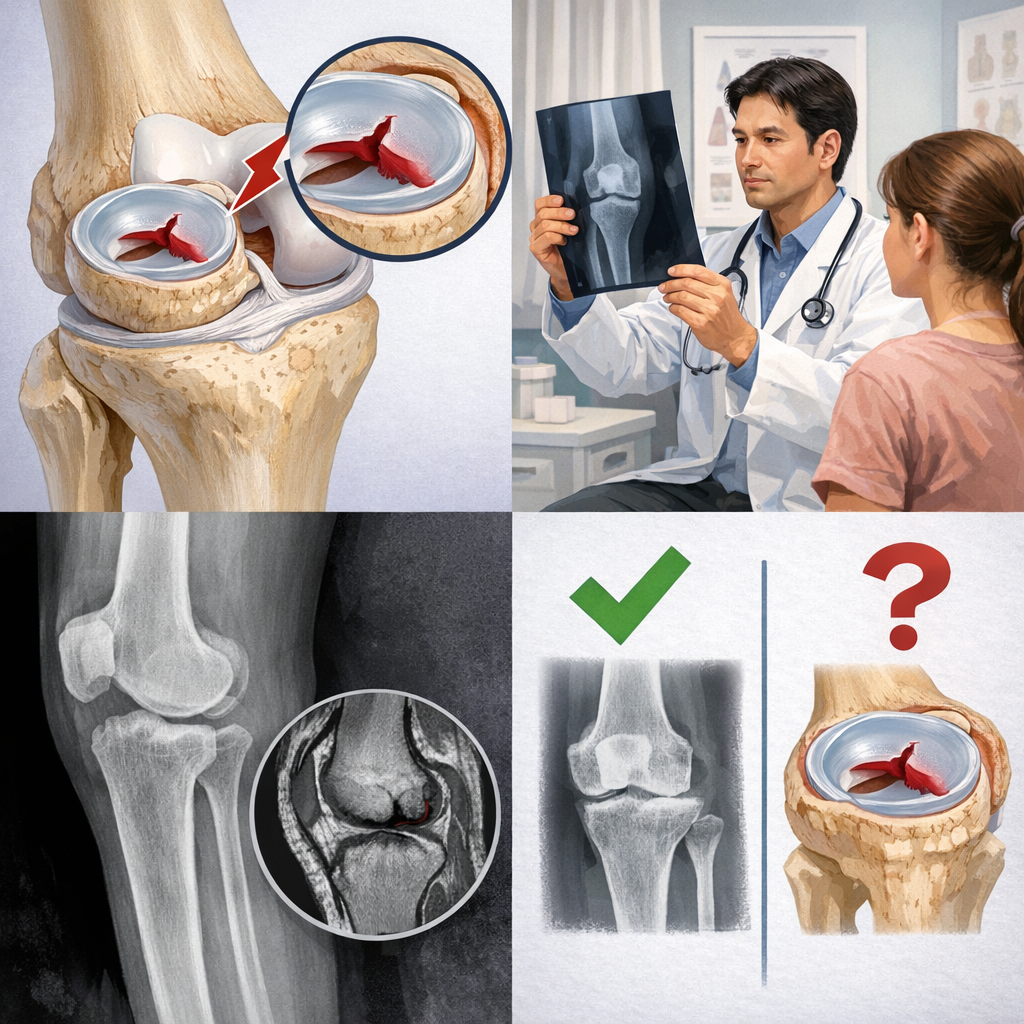

結論から言うと、半月板損傷はレントゲンだけでは診断できません。

ですが、レントゲンにも大切な役割があります。

レントゲンでは半月板そのものは分かりません。

なぜなら、レントゲンは骨を映す検査だからです。骨折や変形、関節のすき間の広さなどは確認できますが、半月板は写りません。

一方で、変形性膝関節症の進行や骨の状態が分かる点は大きなメリットです。

これにより、痛みの原因が半月板以外かどうかを考える材料になります。

つまり、レントゲンは分からないこともありますが、診断に必要な情報を集める大事な一歩なのです。

半月板がレントゲンに映らない理由は、軟らかい組織だからです。

レントゲンは、硬いものほど白く、軟らかいものほど写りにくい特徴があります。

半月板はゴムのような性質のため、画像に現れません。

MRI検査で分かる半月板損傷の状態

MRIでは、半月板の形や裂け方、どの位置が傷ついているかまで詳しく確認できます。

たとえば、同じ半月板損傷でも、自然に治りやすい軽い損傷と、手術を検討した方がよい断裂では対応がまったく異なります。

MRIがあれば、その判断が可能になります。実際の診療では、「MRIでここが少し傷んでいますが、保存療法でいけそうですね」と具体的に説明できるため、患者さんも治療方針に納得しやすくなります。

このようにMRIは、治療の方向性を決める地図のような存在なのです。

半月板損傷は、レントゲンだけで直接診断することはできません。

しかし、レントゲンは意味のない検査ではなく、骨折や変形性膝関節症など、半月板損傷とよく似た症状を引き起こす原因を見分けるために欠かせない検査です。